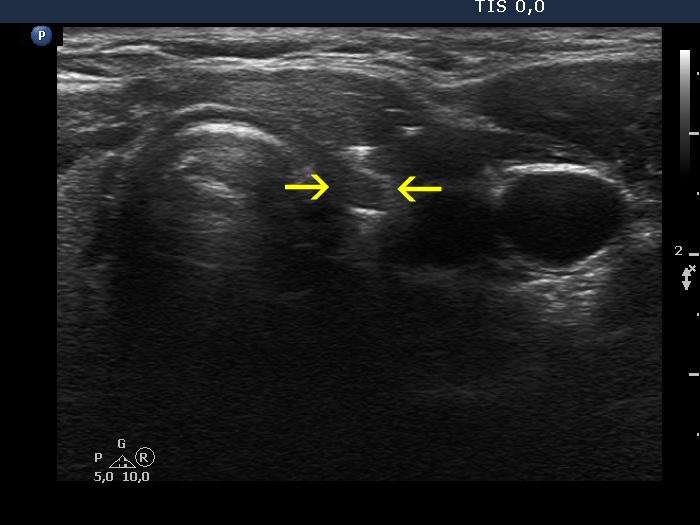

Case 856 (ultrasonographic picture 5b)

Left lobe, transverse scan. There is a tiny, deeply hypoechoic mass marked with yellow arrows. At this time, it is not evident whether this mass is part of the regenerative tissue or corresponds to the thyroid' remnant.